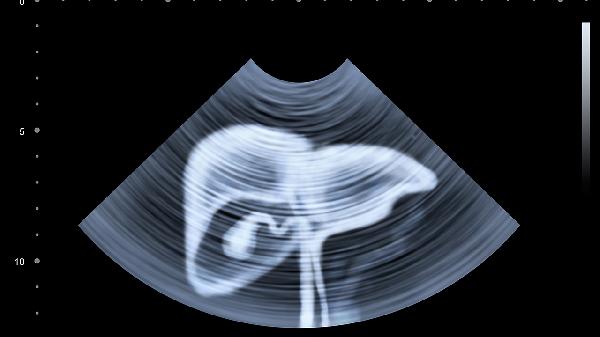

肝脏疾病患者除遵医嘱用药外,需严格戒酒并避免熬夜,每日保证7-8小时睡眠。饮食以低脂高蛋白为主,适量摄入西蓝花、菠菜等富含维生素的蔬菜,限制动物内脏及油炸食品。每周进行3次30分钟以上有氧运动如快走、游泳,避免剧烈运动。定期复查肝功能、超声等检查,出现皮肤黄染或腹胀加重应及时就医。注意个人卫生防护,接种甲肝、乙肝疫苗预防病毒性肝炎。